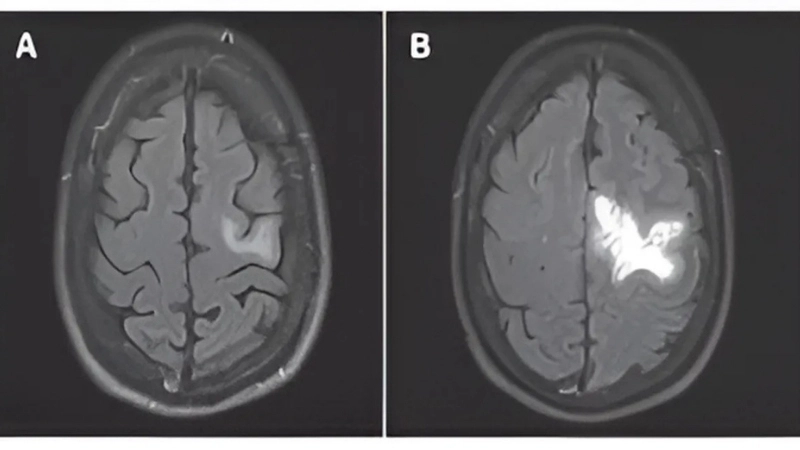

PML diagnosis relies on MRI and JC virus detection